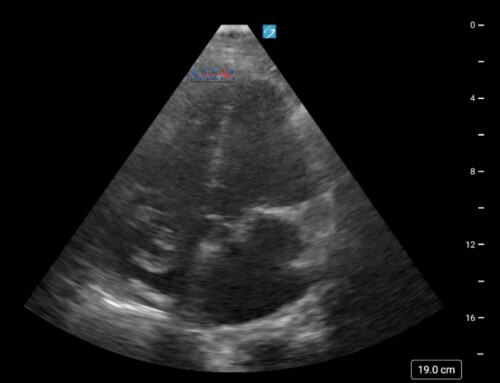

This component emphasizes clinical cases in which ultrasound proved useful for diagnosis (similar to the #US4TW series).

- A clinical case is provided to the learner with an associated ultrasound clip. The learner can then reflect on the differential diagnosis and further work-up prior to clicking the drop down button to reveal the answer and learning point.

Example of the “Clinical Application” Component of the EM Ultrasound website.